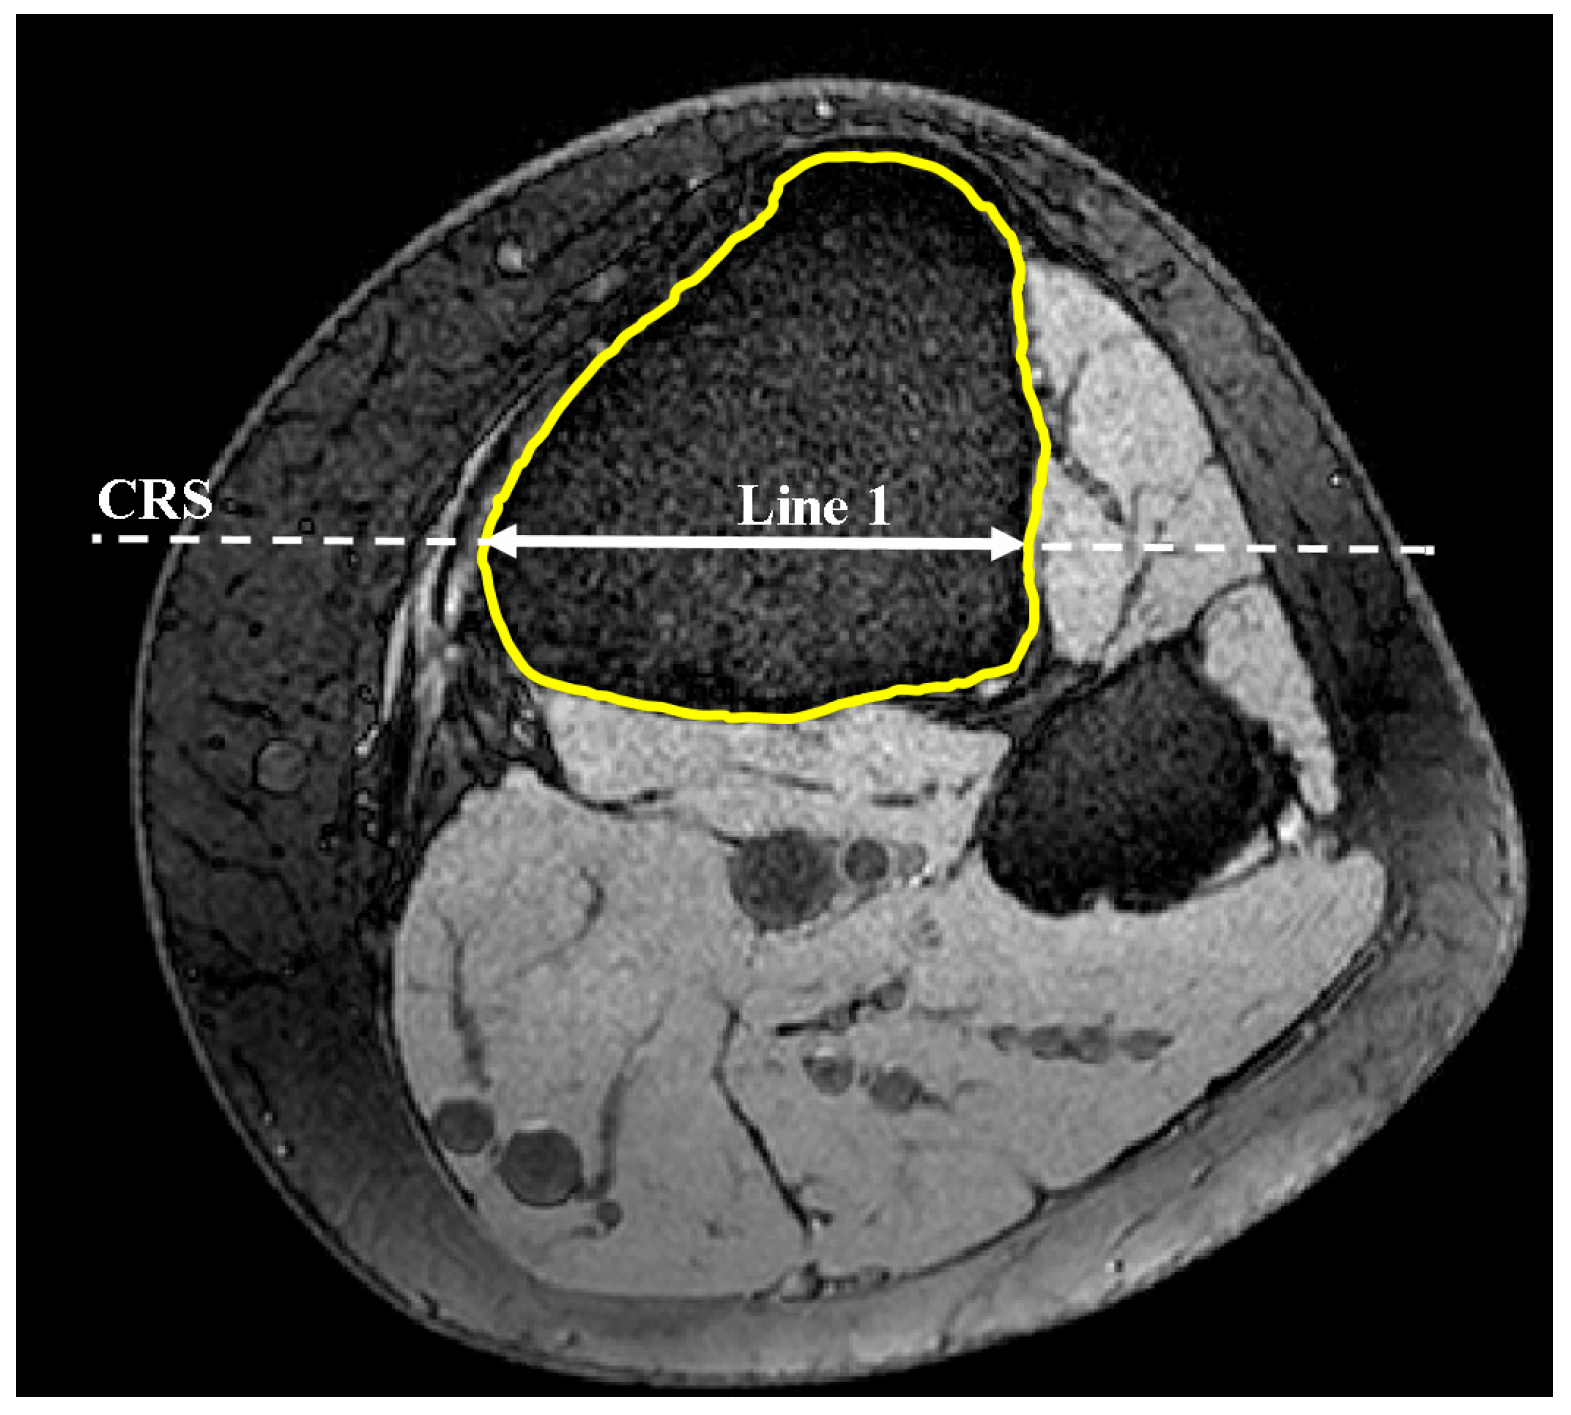

2.2. Coronal Tibial Slope Measurement Method

2.3. Concavity Zone